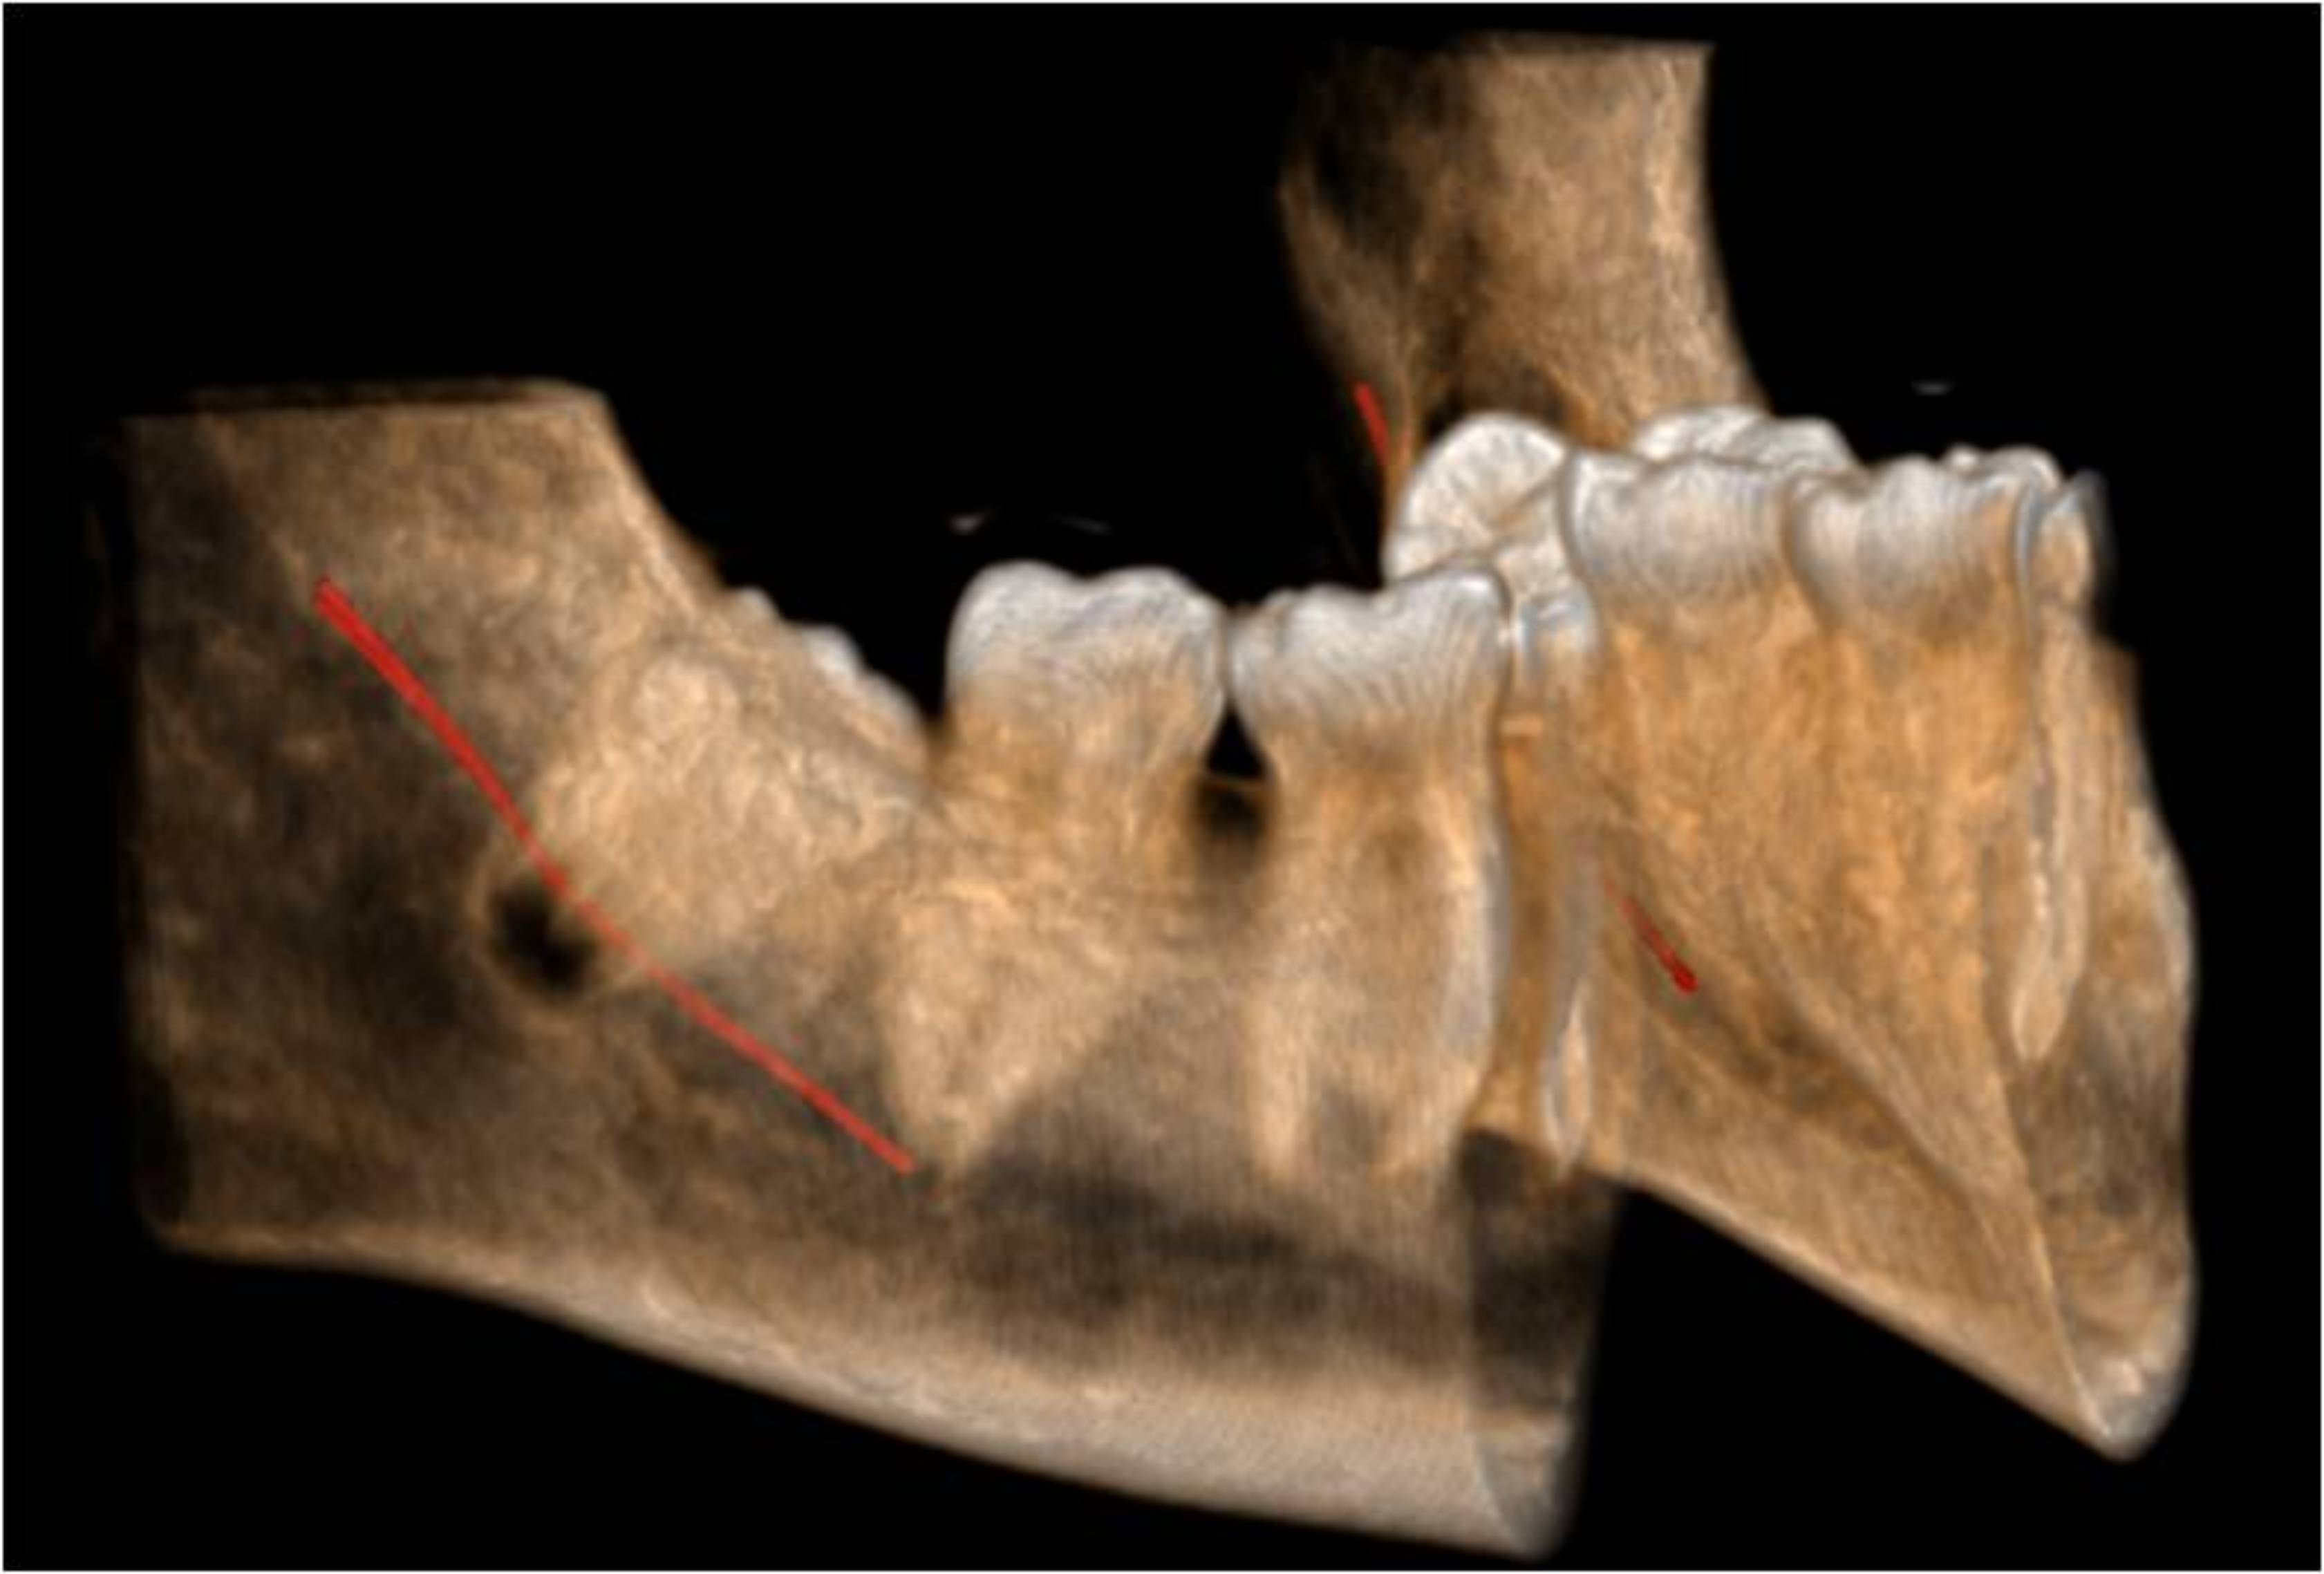

La correcta y clara identificación anatómica de las distintas estructuras comprendidas en la mandíbula son esenciales a la hora de programar una exodóncia de cordales.

De la proximidad de éstos con respecto al conducto dentario dependerá el éxito de la intervención. Nuestros estudios aportan la información en los tres planos radiológicos y herramientas para evitar posibles complicaciones, además de permititr obtener una visión real de todas las estructuras comprometidas en dicha intervención.